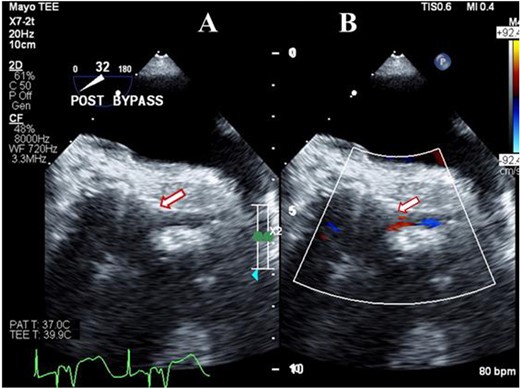

A 56-year-old male underwent AVR for the third time with a 23-mm OnX valve under moderate hypothermic cardioplegic arrest for structural deterioration of bio-prosthetic aortic valve. After suturing the aortic prosthesis, the right coronary artery (RCA) ostium was about 1 cm above, whereas LMCA ostium was relatively close to the prosthesis. Following the removal of aortic cross-clamp, heart resumed activity in ventricular fibrillation and required multiple cardioversions before resuming the sinus rhythm. Subsequently, patient was weaned from CPB on high inotropic support. TEE revealed a well-functioning aortic prosthesis with no paravalvular leak. However, there was severe LV dysfunction with global hypokinesia. The right ventricular function was mildly reduced. A detailed evaluation of the coronary arteries demonstrated severe narrowing of LMCA ostium (Fig. 1A) with turbulent flow (Fig. 1B). A comparison with pre-bypass images confirmed this new finding, whereas RCA caliber and flow were comparable to pre-bypass images.

Transesophageal image following re-operative AVR showing severe stenosis (arrow) at the origin of the left main coronary artery (A) with turbulent flow (arrow) on color Doppler imaging (B).